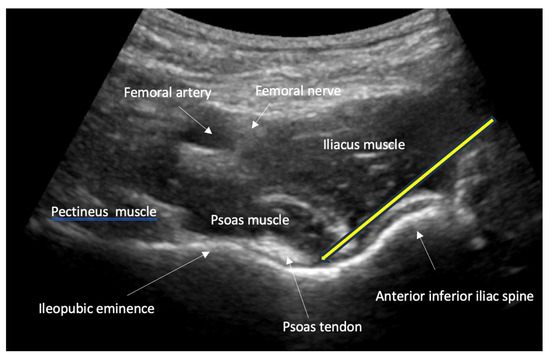

- Nerve, fascia and fascial plane blocks

- Recommendation 8: Simple fascia and fascial blocks are highly suited for analgesia in patients with rib and femoral neck fractures. Local anesthesia using nerve blocks and fracture hematoma blocks should be preferred over analog sedation for fracture reduction whenever possible, as they are less risky.

- For simple fascia and fascial blocks, such as rib and femoral neck fractures. Local anesthesia using nerve blocks is preferred to analog sedation for fracture reduction.